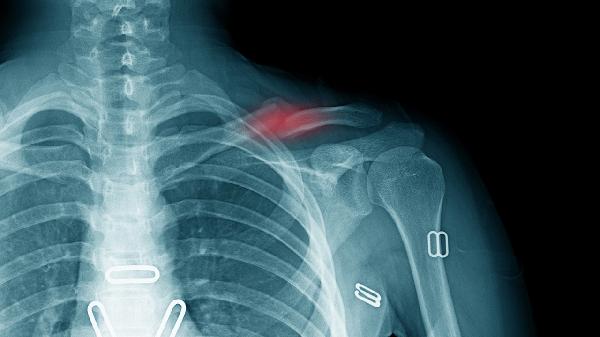

4、胸锁关节紊乱

该关节半脱位或劳损会导致锁骨内侧端压痛,常见于单侧提重物或外伤后。关节活动时有弹响感,X线检查可明确诊断。急性期需固定制动,配合洛索洛芬钠片消炎镇痛,慢性期可通过关节松动术改善功能。康复阶段应加强胸小肌拉伸训练。